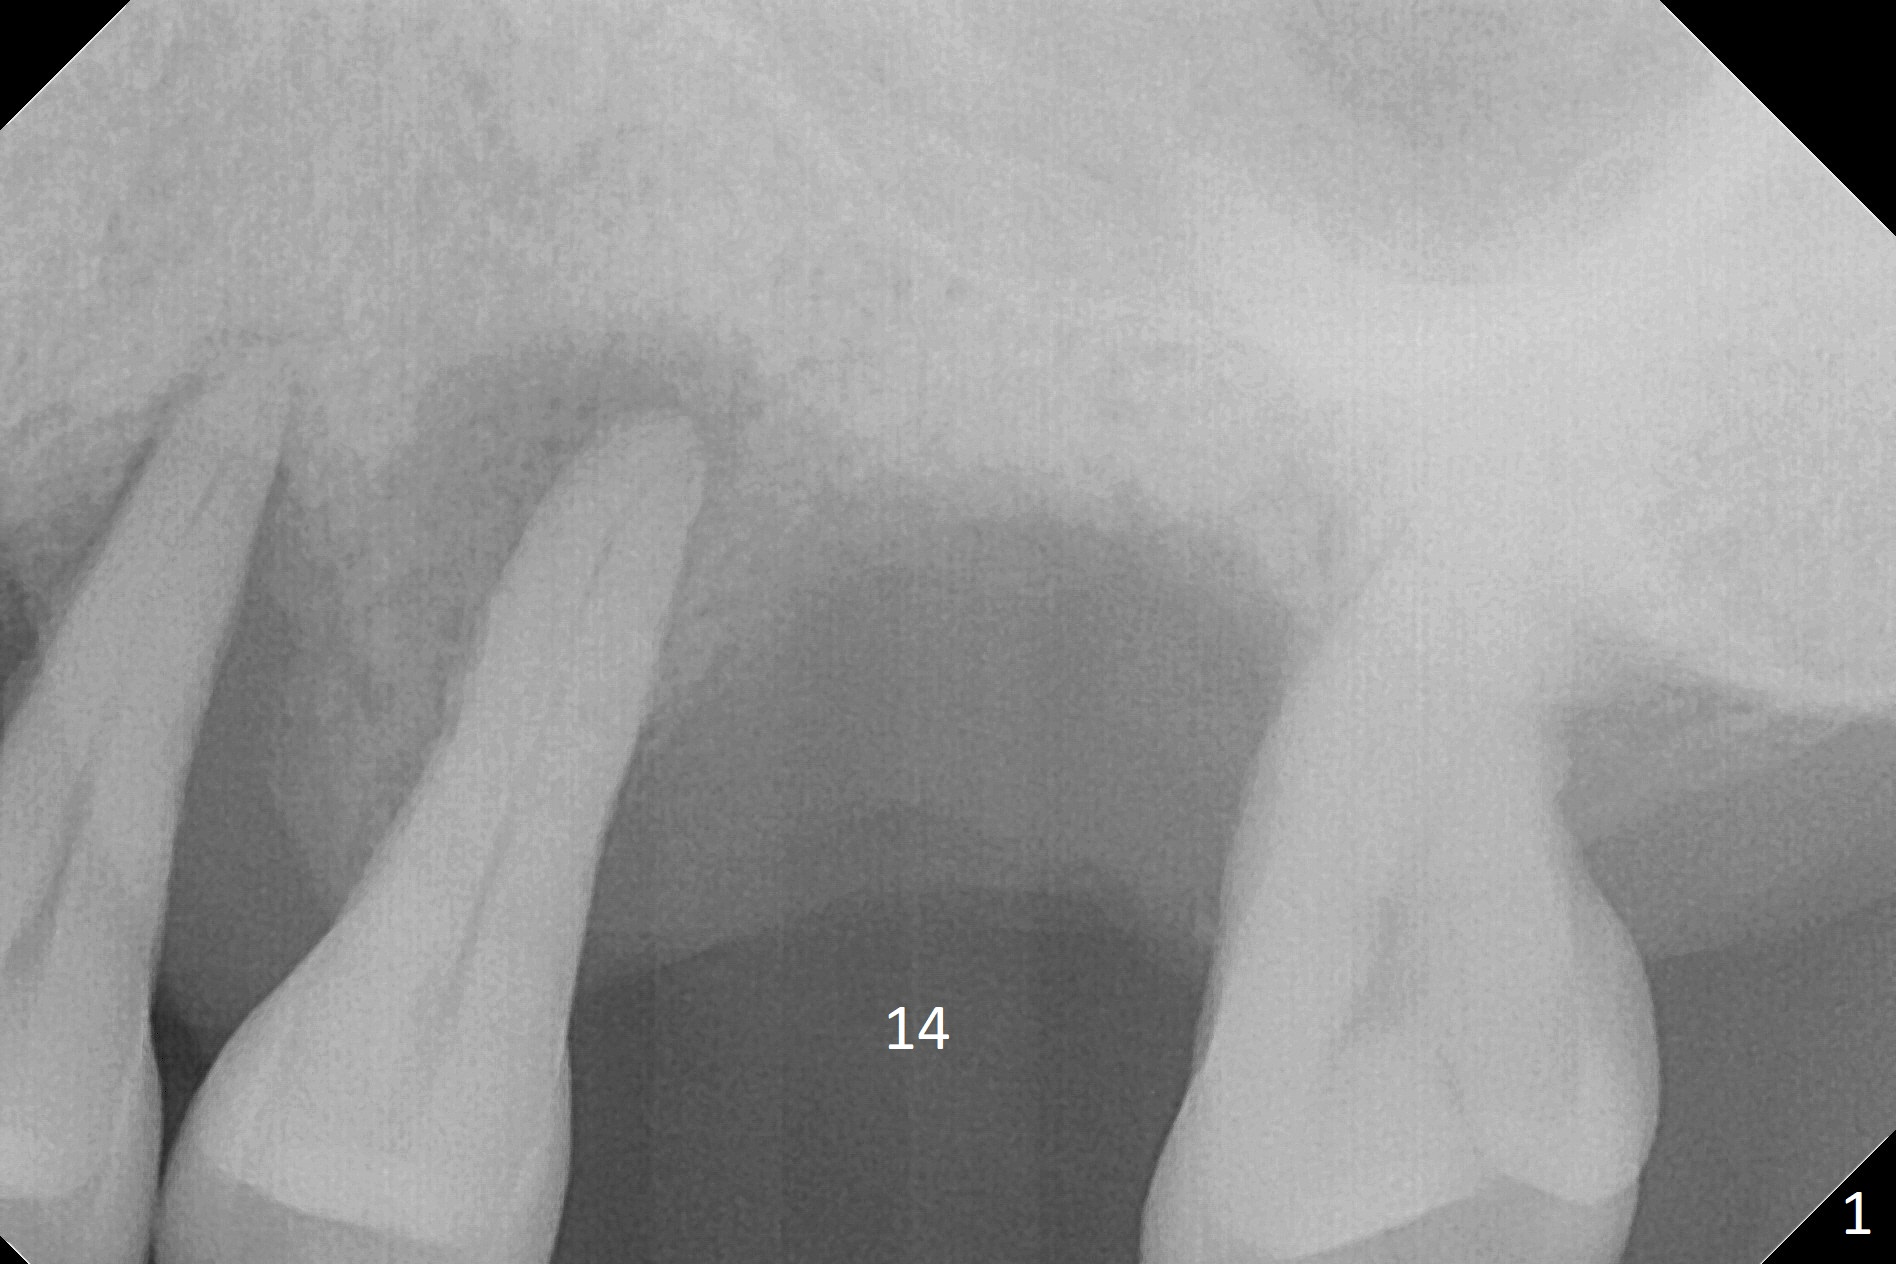

Bone height at #14 two months post exfoliation is ~ 4 mm (Fig.1). Bone expansion is difficult because of dense bone. After drilling, a 4.5 mm tap is inserted with stability (Fig.2). Sinus lift is accomplished with RT3 and autogenous bone prior to placement of a 4.5x8.5 mm implant (Fig.3). Because of flapless surgery and tight and long gingiva, bone graft around the coronal end of the implant is intentionally not placed. A 5.5x5(4) mm abutment is immediately placed for an immediate provisional. (Fig.4). Take PA and impression when the patient returns. The provisional dislodges 3.5 months postop (Fig.4); impression is taken. The patient reports hot sensitivity and pain after meal at the implant site (Fig.5). After removal of the implant crown/abutment, she feels better. If not, it seems necessary to extract the tooth #13 for a 13 mm long implant with a mill abutment (Fig.6).